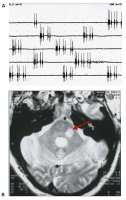

Fazialis-Myokymie

Abbildung 8a-b: Fazialis-Myokymie. (a) Ableitung mit konzentrischer Nadel-elektrode aus dem M. orbicularis oris links. Auftreten spontaner Entladungsserien (Doublets, Multiplets). (b) MRT: Demyelinisierungsherd im Kleinhirnbrückenstiel im Verlauf des intramedullären N. facialis links.